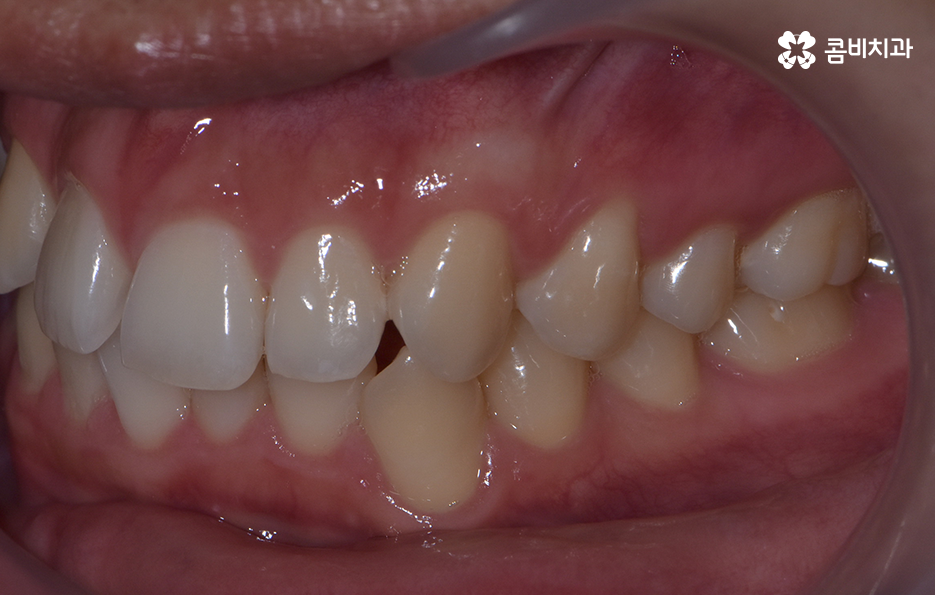

덧니로 인해 치아교정을 고민하시는 분들이라면 대표적으로 발치교정에 대한 고민이나 얼굴 변화, 적합한 교정기의 선택 등에 있어서 많은 고민도 되고 걱정도 되실텐데요

치아교정은 이처럼 어렵게 결심하고 고민해서 시작하는 만큼 무엇보다 초기에 치료 계획과 목표를 잘 정해야 하며 치료가 시작되면 마무리까지 잘 진행되어야 하기 때문에 무엇보다 함께할 교정 전문의를 잘 선택해야 하며 중간에 의료진이 바뀔 우려는 없는지 잘 체크하여 사후관리까지 믿고 찾을 치과를 잘 판단하시길 바라고 있어요